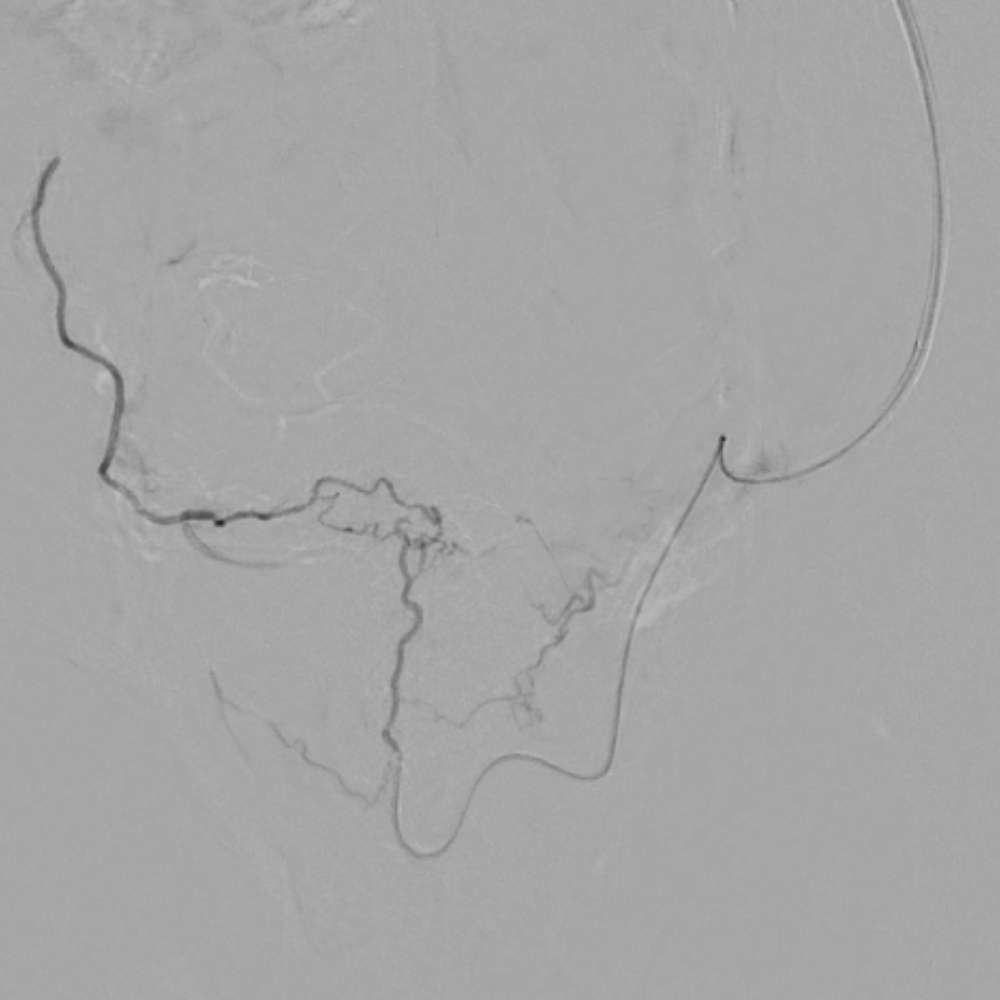

תמונות מהצנתור:

- במהלך הפעולה: החדרת החלקיקים לעורקים המזינים, כעת רקמת הערמונית אינה מקבלת אספקת דם והעורקים הראשיים נצפים. מזריקים משמאל והעורק הראשי מימין מתמלא אך לא רקמת הערמונית שנחסמה.

- לפני החסימה: נראית זרימה עשירה לעורקי הערמונית המוגדלת, הצנתר נמצא בצד שמאל ובעת הזרקת חומר הניגוד ישנם עורקים משותפים לשמאל וימין. כאשר מזריקים את חומר הניגוד מצד שמאל, צד ימין מתמלא באופן מלא. המצב יכול לרמז על היצרות או חסימה במוצא עורק הערמונית הימני.